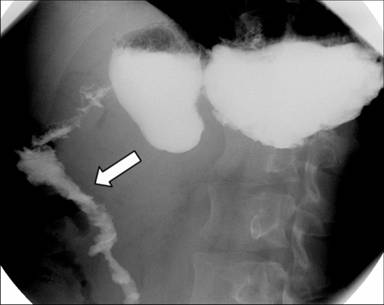

The postoperative course was uneventful. Cholangiography and a barium meal (Figure 11) on the 7th postoperative day revealed no leaks and good functioning of the neoduodenum and choledocho-pancreaticojejunostomy. The bile drain was removed 4 weeks later. During the subsequent five-month follow-up, the patient had no symptoms, returned to work and gained 6 kg.

Figure 11. X-ray barium meal examination seven days after the pancreas-preserving resection of the second portion of the duodenum (Case #2). No leaks and good functioning of the interposed jejunal segment (arrow). |

|